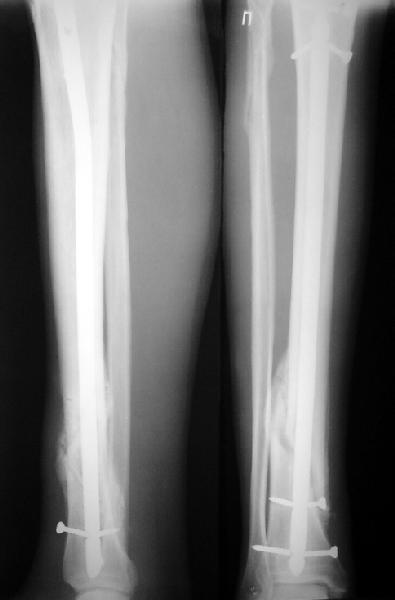

На мой взгляд, на снимках, приведённых Вами - неправильно сростающийся перелом дистальной трети большеберцовой кости, состояние после остеосинтеза интрамедуллярным гвоздём.

Как Вы пишите снимок под номером 1 - менсяц после операции, под номером 2- два месяца после операции.

Вы не послали послеоперационный снимок, поэтому трудно судить о состоянии редукции после операции.

Установка с медиальной стороны гвоздя в области дистального фрагмента дополнительного шурупа помогло бы Вам репонировать и удержать перелом в анатомическом положении, предотвратило варусную деформацию и смещение по ширине.

На мой взгляд внутрикостная фиксация переломов дистальной и проксимальной трети большеберцовой кости, за исключением поперечных, не очень хорошее решение вопроса, аппарат Илизарова или Тэйлора, позволяющие призвести закрытую анатомическую редукцию и отличное удержание отломков в период сращения.

I think that the X-Rays show S/P IMN of Spiral # of the Distal Tibia consoles in misalignment.

You wrote that a picture number 1 - f month after the surgery, and number 2-two months after the surgery.

You have not sent a postoperative X-Rays; so it's impossible to discuss about the condition of a reduction after operation.

Let to express concerning technique of operation my opinion... Insertion of a screw to medial side of a nail in distal fragment would help you to reduction and to keep this fracture in anatomic position has prevented varus deformity and displacement on width. By the way, if it is possible send a postoperative picture.

In my opinion IMN of fracture distal and proximal thirds of the tibia bones, except for transverse, not so good decision of treatment. Ilizarov or Taylor external fixators allow to the closed anatomic reduction and excellent fixation such fractures during the consolidation period.